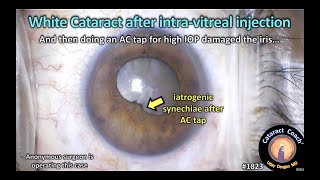

Traumatic cataract after intravitreal anti-VEGF injection. CataractCoach™1823: white cataract after intra-vitreal injection

CataractCoach™1823: white cataract after intra-vitreal injection After cataract surgery what you should and shouldn't do | Dr. Sanket Bhatnagar | Narayana Nethralaya

Traumatic cataract after intravitreal anti-VEGF injection. CataractCoach™1823: white cataract after intra-vitreal injection

CataractCoach™1823: white cataract after intra-vitreal injection After cataract surgery what you should and shouldn't do | Dr. Sanket Bhatnagar | Narayana Nethralaya